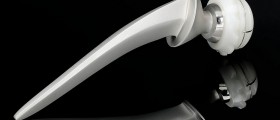

This operation is also known as hip arthroplasty. It includes the removal of the damaged joint and its replacement with an artificial one. This artificial joint is a prosthesis, and it comprises a socket and a ball component. The prosthesis is made of specific material which cannot be rejected by the body. It is also resistant to corrosion and degradation.